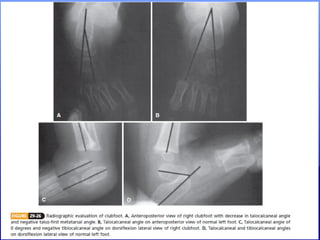

RADIOGRAPHIC EVALUATION

• In a nonambulatory child, standard

radiographs include anteroposterior &

stress dorsiflexion lateral radiographs of

both feet.

• AP & Lateral standing radiographs may be

obtained for older child.

• Important angles to

consider in evaluation

of clubfoot are:

• Talocalcaneal angle

on AP view &

on lateral view & the

Talus-first metatarsal

angle.

• In clubfoot:

• On AP view Talocalcaneal angle is

progressively decreases with increase in

heel varus.

• On lateral view Talocalcaneal angle is

progressively decreases with severity of

deformity to an angle of zero degrees.

• Tibiocalcaneal angle in a normal foot is 10

to 40 degrees on stress lateral view.

• In clubfoot this angle is generally negative,

indicating equinus of calcaneus in relation

to tibia.

• Talus-first metatarsal angle measures

forefoot adduction.

• In clubfoot it is negative, indicating

adduction of forefoot.